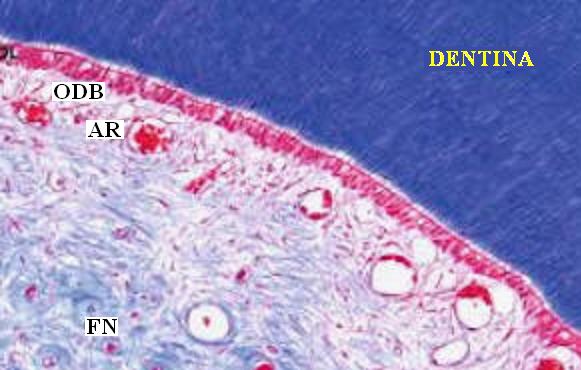

La

Pulpa dental es un órgano junto con la

dentina altamente organizado. (Órgano dentno

pulapar)

Con funciones:

-

de reparación, como es la

producción de dentina secundaria.[14]

-

Metabólicas e

inmunitasrias [22]

-

A lo largo del borde

entre la dentina y la pulpa hay células en

empalizada llamada odontoblastos, que

inician la formación de dentina. [21

-

Su estructura principal

son fibroblastos con una red proteica de

fibrina laxa y vascular arteriovenosa con

fibras nerviosas desmielinizadas

sensitivas.[14]